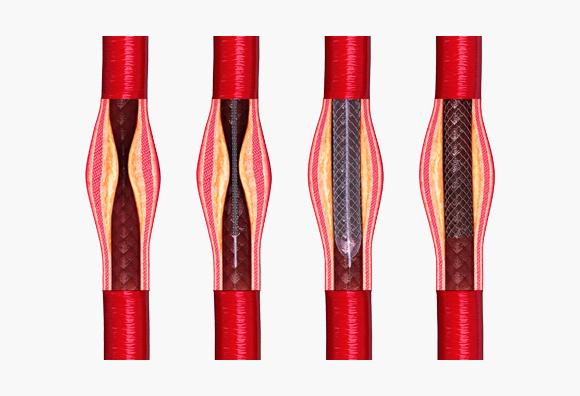

3. 경동맥 풍선 확장술 및 뇌혈관 스텐트 삽입술

<경동맥 풍선 확장술 및 뇌혈관 스텐트 삽입술>

- 신경중재(neurointervention)라는 용어는 다양한 신경계 질환을 두개골이나 척추골 절개 없이 영상 유도(image guidance)하에서 경피적으로 접근하여 치료하는 행위를 말하며, 뇌혈관에서도 동맥경화 등에 의한 협착증이 있을 경우 임상 양상을 고려하여 좁아진 혈관을 넓혀 주기 위해 풍선도관(balloon catheter)을 이용한 혈관성형술을 하거나 필요한 경우 스텐트 삽입술을 실시하고 있습니다.

<경동맥 풍선 확장술 및 뇌혈관 스텐트 삽입술>